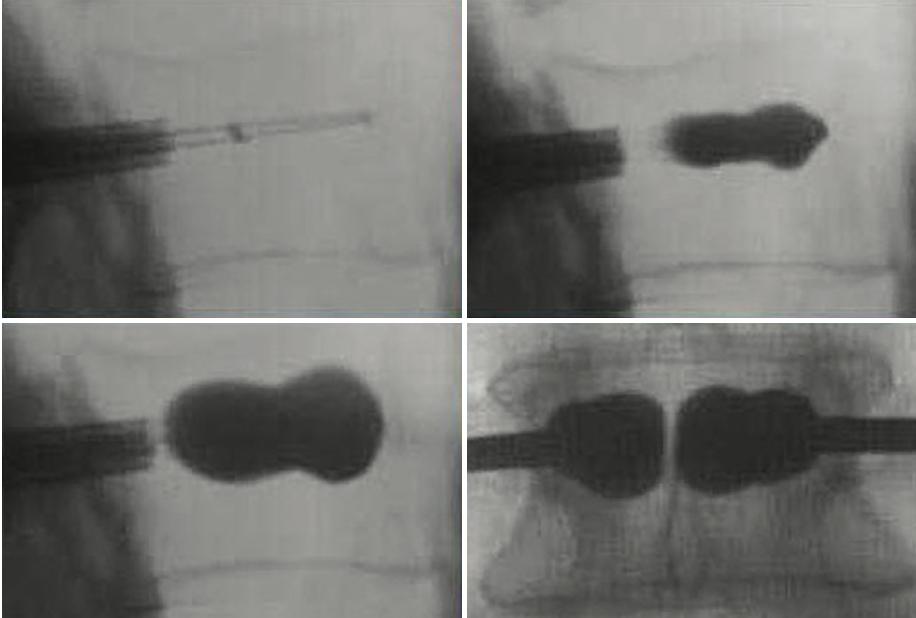

5 Balloondeployment: ballooncathetersareinsertedthrough theaccesscannulasandsubsequentlydeployed Again, imagesaretakentoconfirmcorrectballoonplacement

6 Ballooninflationandcementinjection: Balloontampsare advancedbilaterally Eachballoontamp,attachedtoa lockingsyringewithadigitalmanometer,istheninflatedwith iodinatedcontrast APandlateralimagesareobtained duringinflationtoguaranteesafeandproperepansionand fracturereduction Onceexpansionisadequatelyperformed, balloonsaredeflatedand injectionofcementiscarriedout (cementcannulaisintroducedintoaccesscannulaforthis step). Enoughcementtofillvoidcreatedbyballoonsshould beinjected

Completionofprocedure:cementcannularemovedand styletneedleintroducedintoworkingcannula Oncecement hassecured,cannulais removedunderconstantimagingto detectanyposteriormigrationofcement

Figure14:IllustrationofKyphoplastyprocedure A)lateralfluoroscopicimagesofbonecementcannula insertion(topleft),ballooninflation(topright),bone cementevenlydistributedinvertebralbody(bottomleft), APviewofbilateralballoonkyphoplasty(bottomright) B)simplifiedillustrationofprocedure;needleadvanced intovertebralbody(topleft),ballooninflated(topright), balloondeflatedandcementinjected(bottomleft), cementin-situ(bottomright)